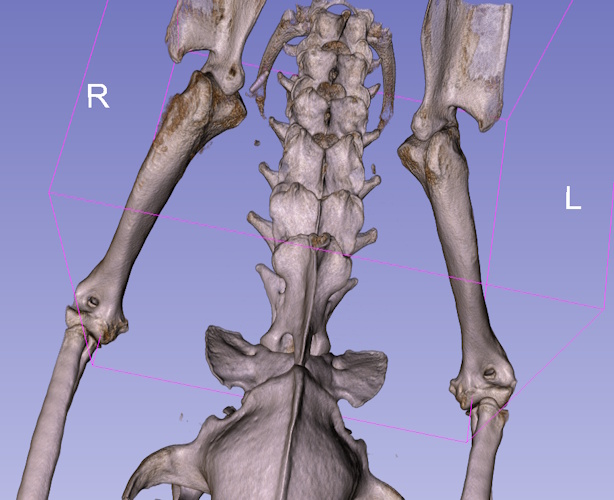

3) Synovial Cell Sarcoma - hindlimb lameness

Toffee, 10yr springer spaniel was admitted through our emergency department for an acutely painful stifle. Radiographs of his hind leg were obtained and sent to a radiologist for interpretation. The report came back identifying a swelling in the stifle (knee) along with mild degenerative changes, which they erroneously attributed to a suspected meniscal cartilage or cruciate ligament injury. Toffee was referred to our orthopedic department for TPLO surgery. Upon examining Toffees leg, things immediately did not add up. He was extremely painful when his stifle (knee) was palpated, yet no instability resulting from cruciate ligament was identified. After reviewing the original radiographs, additional radiographic changes that were previously missed were identified in the distal femur which raised suspicion for a neoplastic (cancer) cause of the lameness. Before exploring the stifle for ligamentous or cartilage damage, advanced imaging was recommended to rule out cancer. The CT scan revealed aggressive change in the distal femur, proximal tibia and around the sesamoids that was consistent with a synovial cell sarcoma or chondrosarcoma.